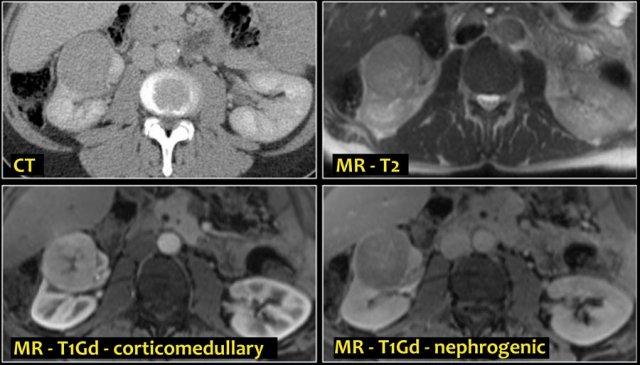

Tổn thương thâm nhiễm ở cực trên thận phải, hầu như không thấy trên ảnh không tiêm thuốc (bên trái), thấy rõ ràng ở thì thận (bên phải). Giải phẫu bệnh xác nhận RCC tế bào sáng

Trong số tất cả các RCC tế bào sáng, khoảng 5% có kiểu tăng trưởng thâm nhiễm.

Mặc dù đây chỉ là một tỷ lệ nhỏ trong số các RCC, nhưng tần suất chung của RCC khiến đây trở thành một chẩn đoán phân biệt quan trọng đối với tổn thương thâm nhiễm dạng hình đậu (bean-type).

RCC thâm nhiễm có tính chất xâm lấn cao và tăng sinh mạch máu.

Tổn thương làm thay đổi cấu trúc nội tại của thận nhưng vẫn bảo tồn đường bờ thận. Các bất thường hệ thống đài bể thận có thể tương tự như những gì thấy trong ung thư biểu mô tế bào chuyển tiếp (transitional cell carcinoma).